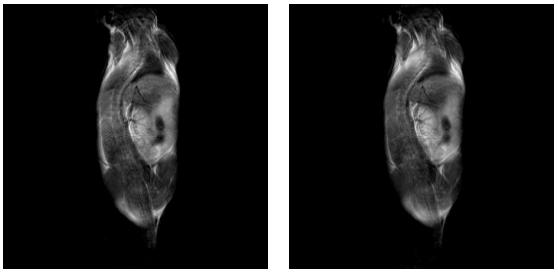

4、核磁共振成像科研性实验样品观察(小鼠,小动植物体等样品的三维、二维成像实验),小鼠分子影像科研实验研究;

肿瘤鼠图片